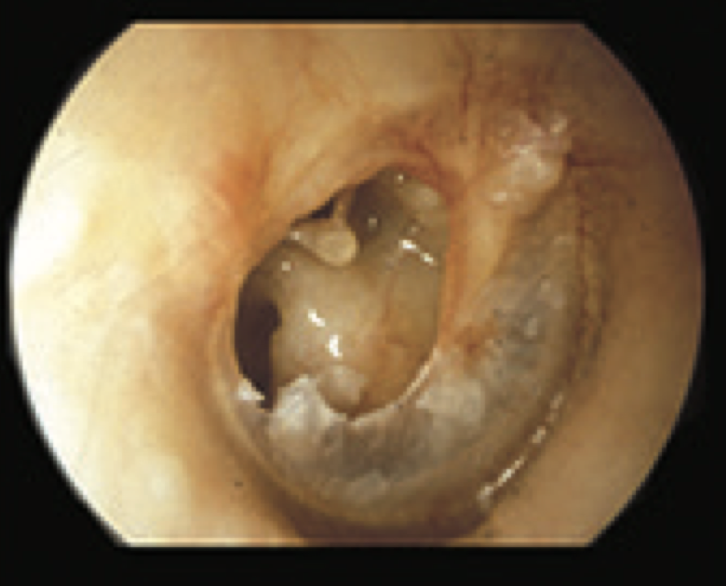

11

Q

What is this?

A

Wet cholesteatoma

- TM with tympanosclerosis

- large attic perforation